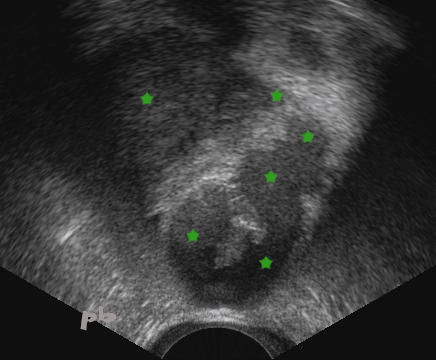

5- Tubal endometriosis – Ultrasound

Increasingly intense cyclic pelvic pain.

Hypoechoic, hematoma-like image (►) located at the right uterine horn, near the endometrial cavity (★).

Uterine contours (►).